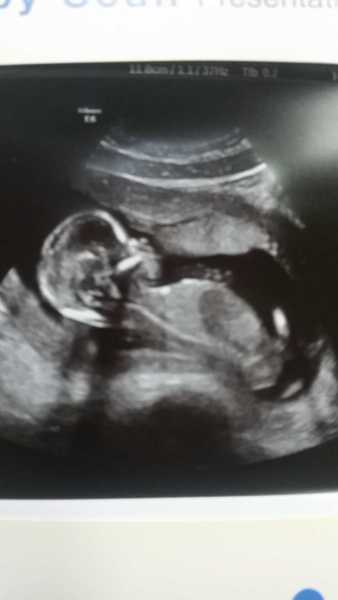

Here's baba lol dd said it was a mermaid!! Son says looks like a penguin haha! 15wks 1 day all fine xx

Gorgeous pic Bex!

Beautiful bex!